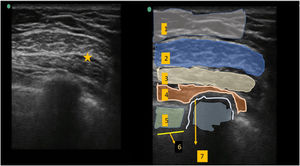

Bloqueo Pecs IILa sonda ecográfica se situó bajo el tercio lateral de la clavícula. Tras localizar la arteria y vena axilares, se movió distalmente la sonda hacia la axila, hasta identificar el músculo pectoral menor, que se utilizó como referencia hasta identificar el músculo serrato anterior al nivel situado entre la 3ª y 4ª costillas. Tras reconocer las estructuras anatómicas adecuadas, se realizó el bloqueo utilizando un abordaje dentro del plano medial-lateral con una aguja de bloqueo de calibre 20. Utilizando hidrodisección salina, se hizo avanzar la aguja al plano tisular entre el músculo pectoral mayor y pectoral menor: se inyectaron 10 mL de ropivacaína al 0,5% (fig. 1). De modo similar, se inyectaron 20 mL de ropivacaína al 0,5% entre el músculo pectoral menor y el músculo serrato anterior (fig. 2).

Se situó la sonda ecográfica a unos 2 cm en paralelo al eje longitudinal del hueso esternón. En primer lugar, identificamos las costillas y la pleura, y en un plano más superficial el músculo pectoral mayor y los músculos intercostales. Se hizo avanzar una aguja de bloqueo de calibre 20 hasta situar la punta en el plano fascial entre el músculo pectoral mayor y los músculos intercostales, inyectándose a continuación 10 mL de ropivacaína al 0,25% (fig. 3).